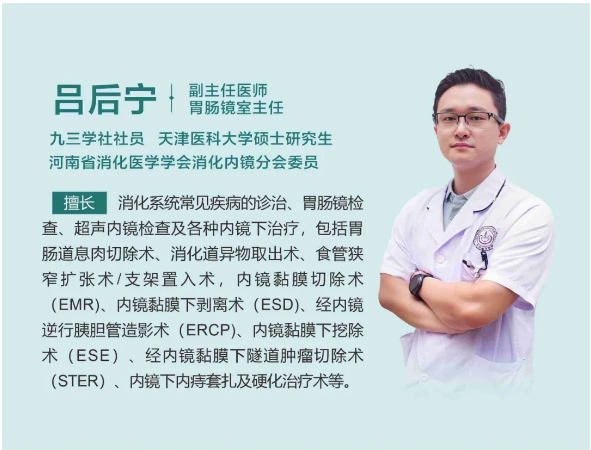

在浏览医院公众号时,小张留意到洛阳白马医院正在开展胃肠镜惠民检查活动,便预约了消化内科的就诊号。接诊的吕主任详细询问了他的症状和病史,结合他的情况,当即为他安排了无痛胃肠镜检查。

检查过程中,内镜医生有了意外发现:小张的食管部位长有一个形似花朵的乳头状瘤。吕主任介绍,食管乳头状瘤在临床中并不常见,尤其是在年轻男性群体中更为少见,其发病多与病毒感染相关,比如HPV病毒。幸运的是,发现及时,肿瘤尚处于早期阶段,医生随即为小张进行了内镜下切除术,整个过程顺利完成。

吕主任表示,像小张这样的案例并非个例。很多年轻人对消化道的轻微不适不以为意,觉得“忍忍就过去了”,殊不知一些看似普通的症状,可能是身体发出的健康警报。食管乳头状瘤虽然恶变概率相对较低,但如果长期忽视,也存在病变风险。而胃肠镜检查作为消化道疾病筛查的“金标准”,能够直接观察到食管、胃、肠道黏膜的细微变化,实现早发现、早诊断、早治疗。

“尤其是有消化道不适症状,比如反复腹痛、腹胀、反酸、排便习惯改变等,或者有消化道疾病家族史、长期存在不良生活习惯的人群,更应该重视定期筛查。”吕主任强调,“现在的无痛胃肠镜技术已经非常成熟,检查过程舒适,安全性高,不用有太多顾虑。”